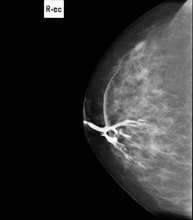

Mammography-guided stereotactic biopsy

The presence of clustered microcalcifications may be an early form of breast cancer. Stereotactic biopsy is used to diagnose these small lesions. In this procedure, the lesion is located on the mammogram and a computer connected to the mammography machine uses a guidance system to determine the exact point and depth of the puncture. The radiologist performs the biopsy after administering local anaesthesia to the area, removing several millimetre-sized fragments of the lesion (5 to 10) so that the pathologist can then diagnose the condition. The average duration of the procedure is 20 minutes and causes slight discomfort.

Pre-surgical harpoon marking

Small, non-palpable breast lesions requiring limited surgery, which need to be marked prior to the procedure by placing a harpoon in the area to be examined. The harpoon is a thin wire with an angled tip (harpoon) that remains fixed in the designated area of the breast. Under mammographic or ultrasound guidance, the radiologist inserts the harpoon into the lesion, where it remains fixed. This will enable the surgeon to locate the injury safely. The average duration of the procedure is 20 minutes and causes slight discomfort. It is usually performed a few hours before going into the operating theatre, although it can be done the day before.